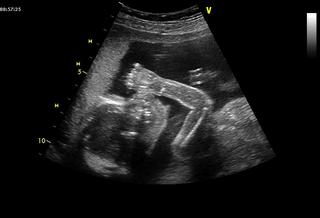

Ináč mám za sebou ďalší UTZ a pridávam fotečku - podarilo sa nám ho z profilu sfotiť, ako si cucá palček. Proste najkrajšie dieťa na svete 🙂 🙂 Ináč všetky "merania" a parametre, ktoré sa dali pozrieť a zisťovať, boli k dnešnému dňu ok, tak som rada. ahojkyy